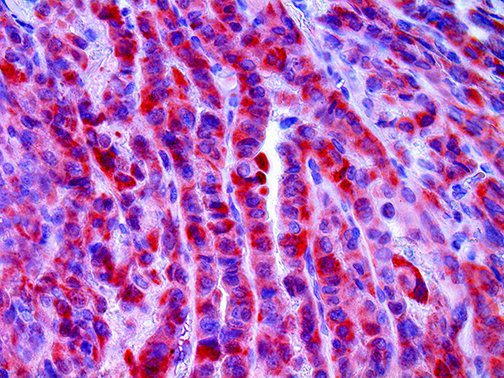

The first cytokines released are interleukin 1β (IL-1β) and tumor necrosis factor-α (TNF-α), which attract a variety of circulating white blood cells (WBCs) to the infection site, including neutrophils, monocytes, macrophages, and natural killer (NK) cells. This response, along with the antipathogenic chemicals released by these cells (i.e., complement), comprise the innate immune response. These cells directly attack the invading pathogen and also release additional cytokines, chief among them interleukin-1 and 6 (IL-6). IL-6 is essential for invoking the adaptive immune response, which calls T-cells, B-cells, and T helper (Th) cells to the infection site. IL-6 also stimulates further recruitment, proliferation and activation of macrophages.

It is the ICU physician who is most likely to witness one of the deadliest manifestations of the abnormal immunological response, the cytokine storm syndrome (CSS). This response is also referred to by some as the cytokine release syndrome (CRS). CSS is characterized by continuous activation and expansion of macrophage and lymphocyte populations, which secrete large amounts of cytokines, causing the cytokine storm. This massive cytokine release is akin to hemophagocytic lymphohistiocytosis (HLH) disease, a syndrome characterized by initial unchecked and persistent activation of cytotoxic T lymphocytes and NK cells.